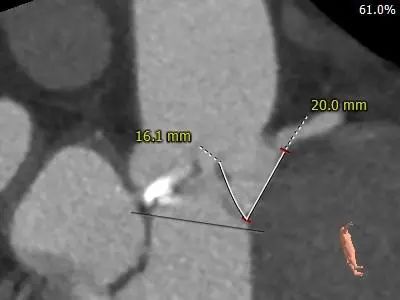

冠脉测量:

冠脉开口高度可,左窦瓣叶长于左冠开口下缘,结合瓦氏窦、STJ内径综合预估,存在一定阻挡风险,术中结合球扩进一步评估,必要时冠脉保护。

推荐22mm球囊预扩,预装AV29瓣膜,可备选22mm球囊预扩,预装AV26瓣膜以降低冠脉风险。